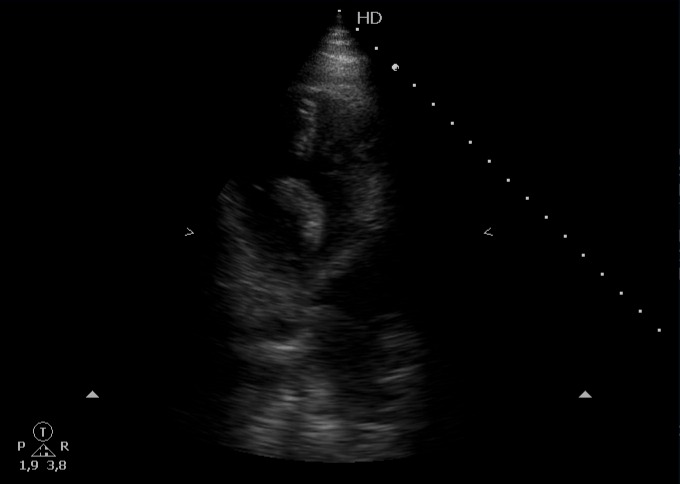

Escalas de riesgo probable para tromboembolismo pulmonar, cursando prueba de imagen que confirma patología y ampliando estudio con ecografía cardíaca que muestra presencia de émbolo intracardíaco.

Clasificación de trombo intracardíaco en Tipo A, B o C; el A tiene forma de gusano o serpiente, es móvil y suele asociarse a TVP.